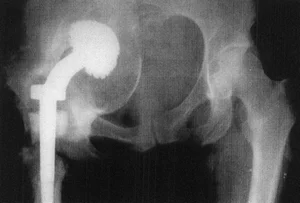

Как видно на приведенной рентгенограмме, после удаления эндопротеза остаётся "пустое место" в области бывшего тазобедренного сустава.

При стоянии или ходьбе на эндопротез ложится большая нагрузка, в соединении между костью и эндопротезом происходят микродвижения. Вследствие этого эндопротез расшатывается. Может расшататься как ножка (бедренный компонент), так и чашка (вертлужный компонент) протеза. Ножка эндопротеза может разрушить стенку кости, в которой расположена - возникает перипротезный (парапротезный) перелом.

При развившейся нестабильности эндопротеза требуется повторная операция - ревизионное эндопротезирование.